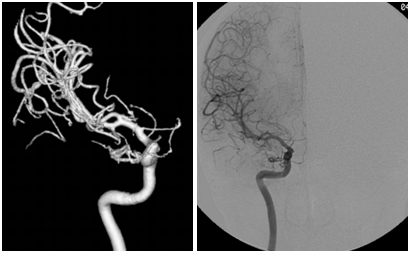

On admission at our Hospital, CT scan demonstrated a focal SAH in the right pericarotid and sylvian cisterns and cerebral angiography showed a small “blister” aneurysm of the infero-medial portion of the right supraclinoid ICA (Figure 2). A right pterional craniotomy with anterior clinoidectomy was performed. A non saccular carotid aneurysm was found: clipping was not possible and wrapping of the arterial dilatation was performed. The exploration of the ICA and its branches did not reveal any changes. Postoperative course was uneventful. At postoperative control angiogram at two weeks the aneurysm was unchanged and stenosis of the right anterior cerebral and posterior communicating arteries due to vasospasm or dissection was present (Figure 3). At one year, the patients remained well and the narrowing was unchanged, confirming the hypothesis of a residual dissection.

Figure 3 3D- Angiographic reconstruction shows stenosis of the right posterior communicating and anterior cerebral arteries (arrow) at postoperative angiogram two weeks after the operation related to possible dissection.

Our second patient may suggest that a special consideration of in-flight sentinel headache and SAH occurring after landing is necessary. This case documents an unusual dissection of the supraclinoid ICA evolving from an initial blister aneurysm with focal leak to a late narrowing of the anterior cerebral artery (Figure 2 and 3). Blister aneurysms constitute a subgroup of carotid aneurysms with fragile wall which may be exposed to the risks of changing transmural pressure.